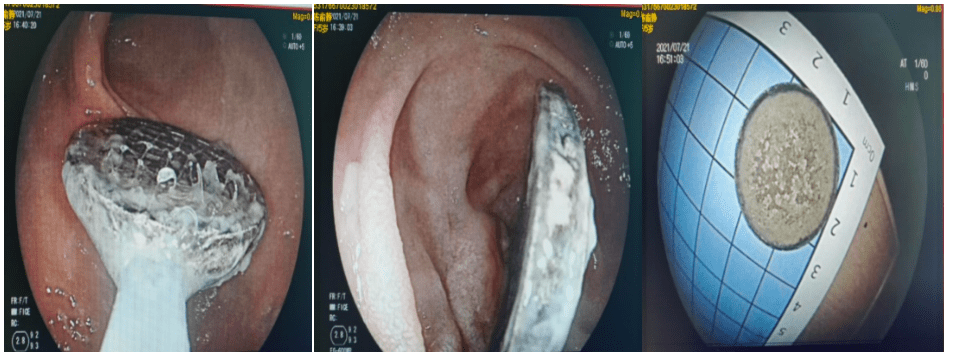

万幸的是 , 当在进入十二指肠降部时 , 突然镜头前面出现了一个被腐蚀的乌漆嘛黑的硬币 。 患儿成功地躲过了一劫 , 避免开腹手术 。 脾胃病科团队用带网篮的圈套器 , 将硬币套牢 , 慢慢地取出;十二指肠降部黏膜有少许糜烂 , 但问题不大!当家属看到取出的硬币时 , 感动万分幸运 , 不停地道谢 。

文章图片

发现和取出的硬币